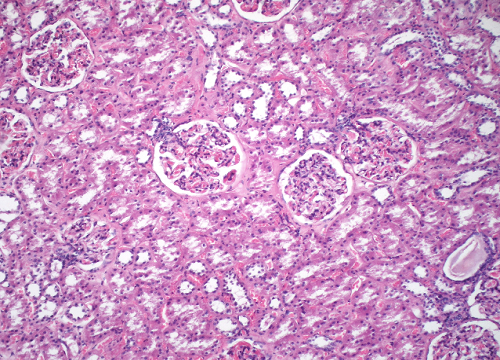

Question 20

Question

Label this image

Image:

96abce79-4d0c-4ab4-a976-04606da596d7 (image/png)

Answer

Kidney